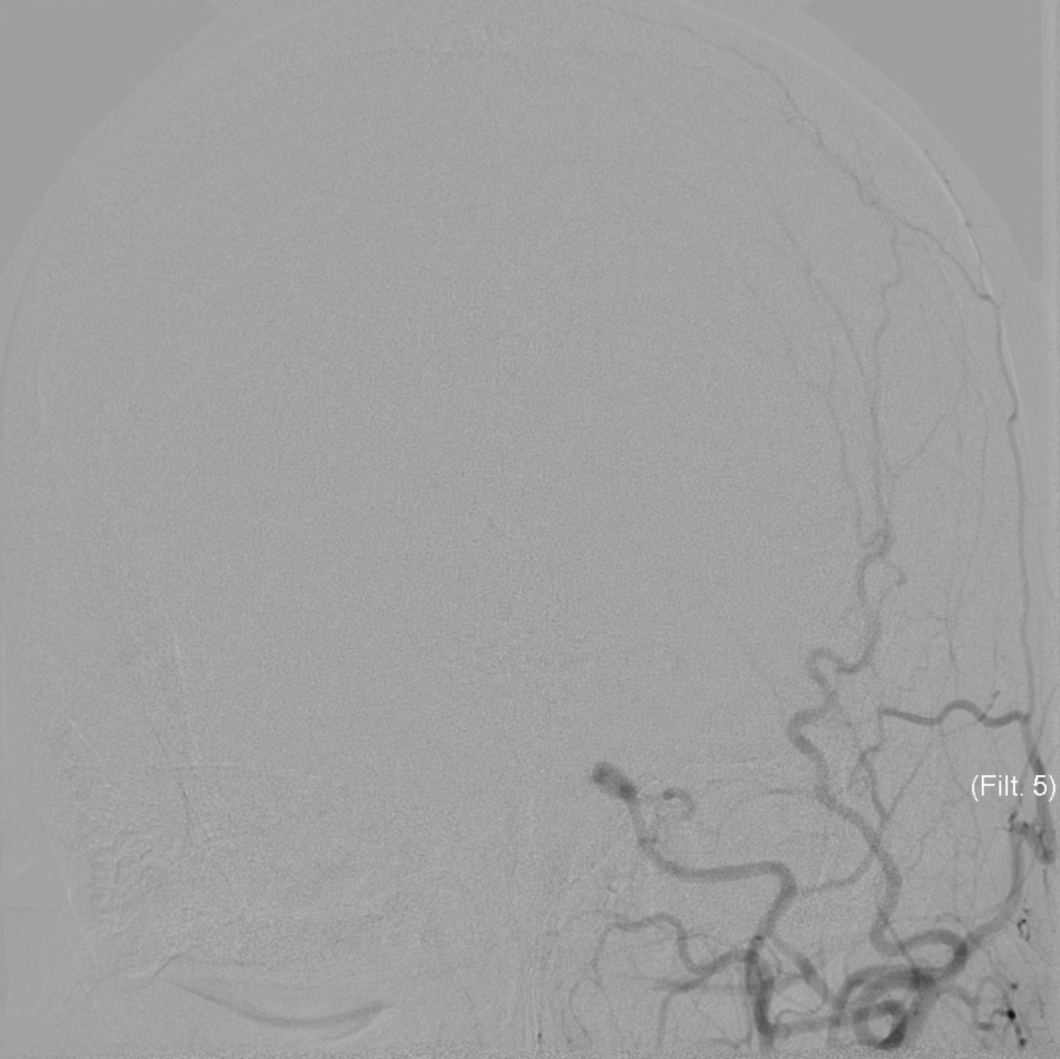

全脑血管造影检显示,龚小姐双侧颈内动脉末端存在闭塞,脑血管分布形似烟雾